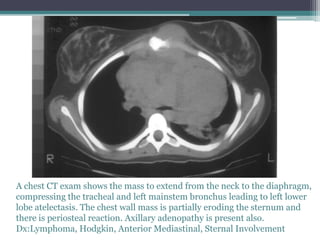

A chest CT exam shows the mass to extend from the neck to the diaphragm,

compressing the tracheal and left mainstem bronchus leading to left lower

lobe atelectasis. The chest wall mass is partially eroding the sternum and

there is periosteal reaction. Axillary adenopathy is present also.

Dx:Lymphoma, Hodgkin, Anterior Mediastinal, Sternal Involvement